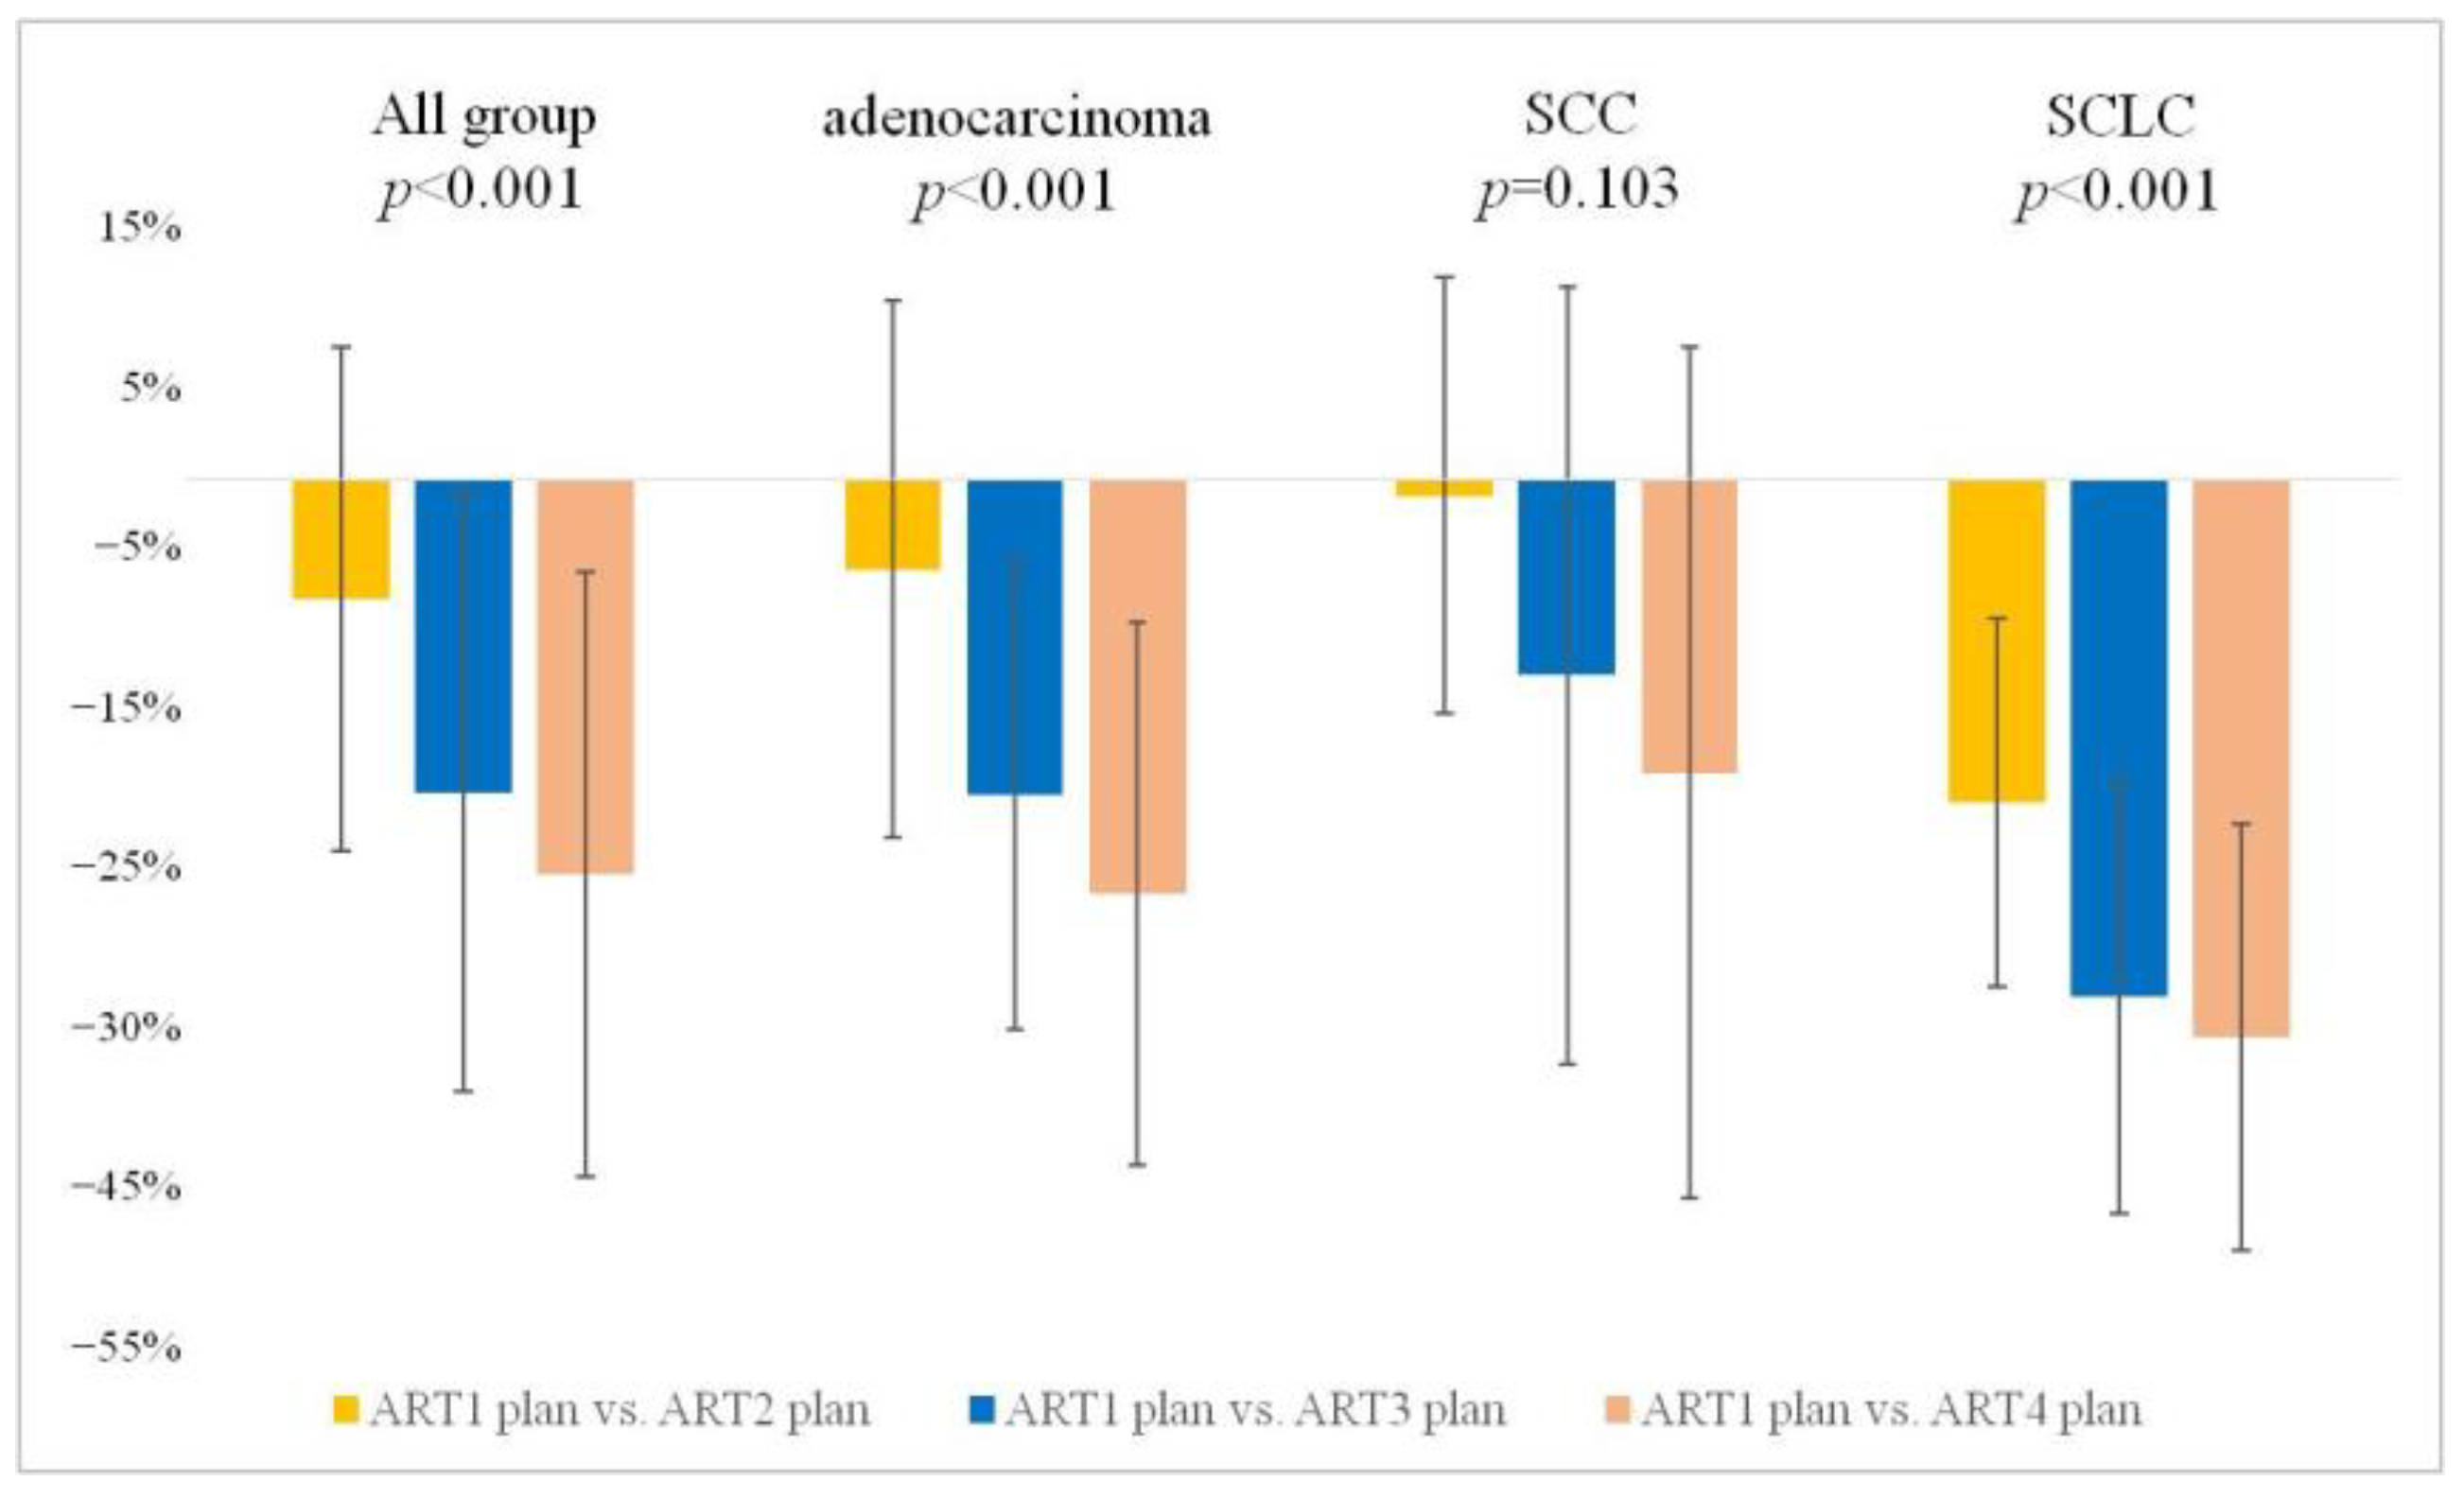

3.3. GTV Changes

3.3.1. Weekly Stepwise Tracking of GTV Changes: A Cumulative Comparison from the Start of Treatment

3.3.2. Weekly Interval Comparison of GTV Alterations